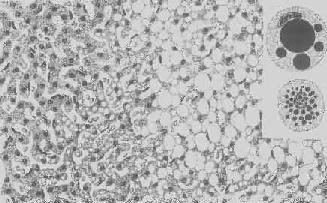

图1-18 肝细胞脂肪变性

肝细胞胞浆内出现大小不等的脂肪空泡;右上角为饿酸染色的脂肪细胞, 脂滴染成黑色